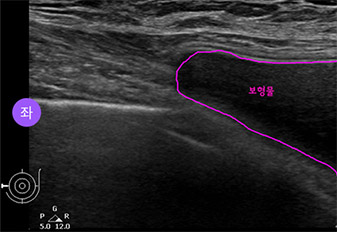

* This is an actual breast ultrasound examination screen after

breast augmentation surgery at View Plastic Surgery. *